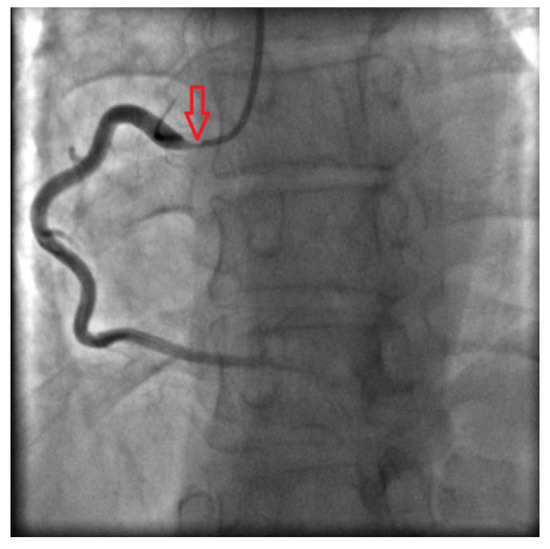

Coronary angiography clarified causes of chest pain: subocclusions of right and left main coronary arteries were found (Fig. 3 and Fig. 4).

Fig. 4. - Right coronary angiogram shows critical ostial stenosis.